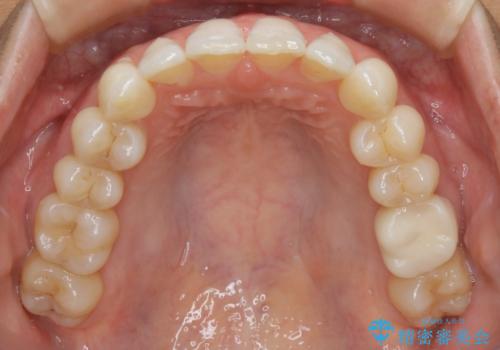

【抜歯】矯正治療とインプラントで正常な噛み合わせを実現

- 元々は矯正治療を主訴にご来院されました。

治療を始めるにあたり、精密検査を受けていただき全体の状況を把握したうえで矯正治療の計画を立てることとなりました。

その過程で左下の6番目の歯は治療が必要な状態であることが分かり、被せ物を外して内部を確認してみると根が破折してしまっていることが判明しました。

歯が深い位置で破折している場合は基本的には抜歯が選択されます。

様々な治療プランを患者さんと相談させて頂き、最終的にインプラントで噛み合わせを回復させていくこととなり、まず悪くなっている歯を抜歯することから開始しました。